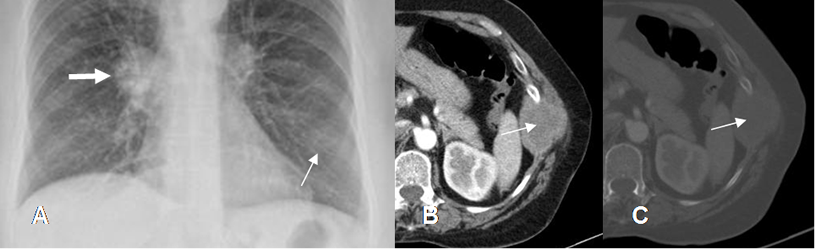

Fig 38. Lesiones extrapleurales.

A y B: Rx PA. Imágenes densas y de bordes bien definidos, que forman ángulos obtusos con la pared costal, indicando ubicación extrapleural.

Fig 39. Lesión extrapelural.

A: Rx PA y B: TAC axial. Imagen densa con ángulos obtusos, que ocasiona destrucción del arco costal, lo que confirman su localización extrapleural.